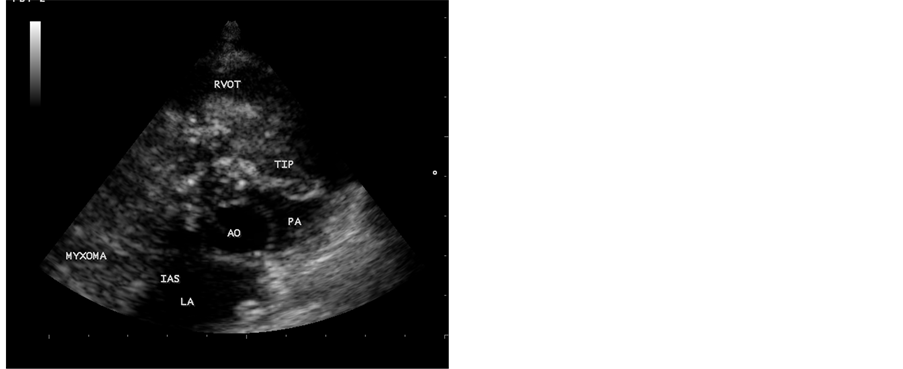

A 12-year-old male child was suffering from low grade fever, joint pains and weight loss for the past two years. He was on penicillin prophylaxis with a suspicion of Rheumatic fever by a local practitioner during this period. Since he developed dyspnea, vomiting episodes and dizziness in the school while sitting in the class room suddenly, he was referred to this hospital. General examination revealed no abnormal findings. His heart rate was 96 bpm and blood pressure was 110/80 mmHg. Physical examination revealed loud first heart sound, a mid diastolic murmur in the lower left sternal edge and a soft midsystolic murmur in the second left intercostal space. The second heart sound was inaudible. These features are consistent with tricuspid and pulmonary valve stenoses and clinically masquerading as right sided obstructive lesions such as Ebstein anomaly, Rheumatic tricuspid valve disease and congenital pulmonary valve stenosis. Lung fields were clear. Blood chemistry revealed normal. ECG revealed large P wave and X-ray chest showed right atrial enlargement and a prominent main pulmonary artery with diminished vascular markings. CT abdomen was normal. Transthoracic 2D echocardiography revealed a large myxoma occupying in the right atrium measuring 69.5 mm × 38.1 mm size with an attachment to the interatrial septum. It is prolapsing through the tricuspid valve into the right ventricle as shown in Figure 1 and extending into the right ventricular outflow tract in Figure 2. It is protruding into the pulmonary artery through the pulmonary valve in Figure 3. Color-flow Doppler Figure 4 and Figure 5 revealed tricuspid and pulmonary valve obstructions as mild to moderate stenoses. The child responded to steroids. He developed the similar symptoms after one week, which are intermittent in nature and died suddenly when leaning forward while washing his face in the early morning hours due to a syncopal episode before planning to surgical removal of the tumor. Echocardiographic screening of family members were normal.

Figure 3. Short axis view, showing the myxoma protruding into the main pulmonary artery through the pulmonary valve.

Figure 4. Color-flow Doppler imaging―Apical 4 chamber view, showing the tricuspid valve obstruction as moderate tricuspid stenosis.

In this case report, a large right atrial myxoma, 69.5 mm × 38.1 mm in size, with a basal attachment to the entire portion of interatrial septum, prolapsing into right ventricle through the tricuspid valve and it’s floating part protruding into the main pulmonary artery in a 12-year old male child was visualized by transthoracic 2D echocardiography. Figures 1-3 revealed the myxoma occupying in the right atrium and prolapsing into the right ventricle through the tricuspid valve, extending into the right ventricular outflow tract and protruding into the pulmonary artery through the pulmonary valve. Color-flow Doppler Figure 4 and Figure 5 revealed the tricuspid and pulmonary obstructions as moderate stenosis of the valves.